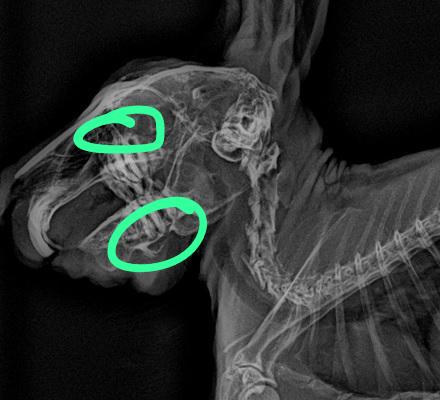

門牙感染、充滿膿液

牙根過長(食物太過多樣化、兔兔挑食誘發只食甜食,拒食硬草)

2. 影像檢查:X 光可評估腸道氣體、糞塊位置和牙齒結構;或需鎮靜。

• 牙科問題:在麻醉下修整牙齒,移除尖刺,或處理牙根膿腫。術後需服用止痛及抗生素。